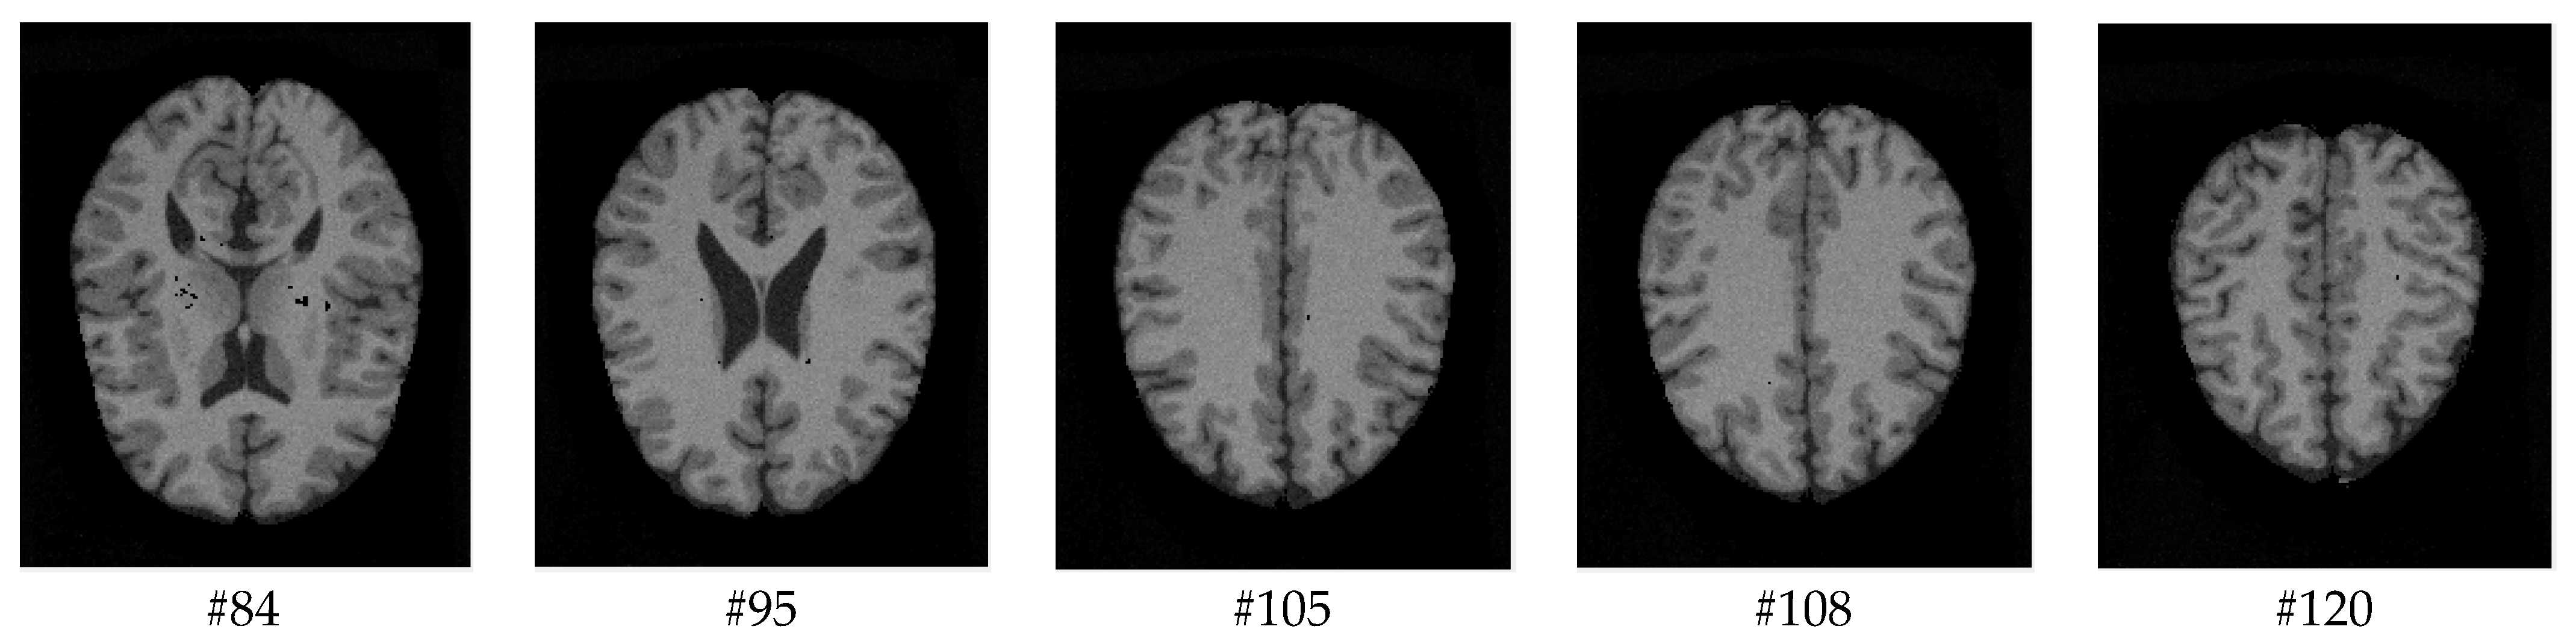

As mentioned before, the images of the first five datasets in Table 3 were used to evaluate the performance of the HMRF-WOA. Figure 1, Figure 2, Figure 3, Figure 4 and Figure 5 show some slices of a T1-weighted image (slices: 84, 95, 105, 108, 120). These brain images correspond to the slices under different types of conditions, such as database type, dimension image, noise level, intensity non-uniformity level, and slice thickness (mm). In Table 1, rows 1 to 5 summarize the parameters of Figure 1, Figure 2, Figure 3, Figure 4 and Figure 5, respectively. Figure 6 represents the ground truth segmentation of slices 84, 95, 105, 108, and 120. In this figure, each column contains the three tissues, GM, WM, and CSF, of each slice. Figure 7, Figure 8, Figure 9, Figure 10 and Figure 11 show the segmentation results, where the four tissues (BG, GM, WM, and CSF) are shown with different colors. The yellow, red, and green colors represent the segmented regions of GM, WM, and CSF, respectively. As we can also see from these figures, the resulting segmented images in Figure 7, Figure 8, Figure 9, Figure 10 and Figure 11 are almost close to the initial images in Figure 1, Figure 2, Figure 3, Figure 4 and Figure 5.

Figure 5. Slices with Noise = 9%, INU = 40% of database 5.